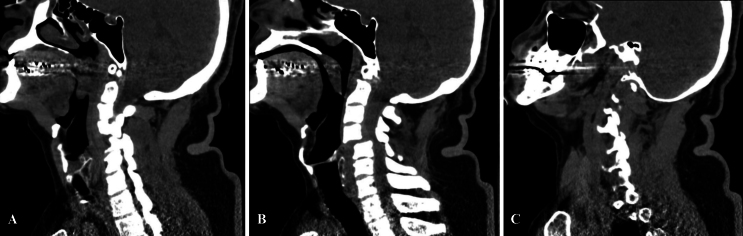

A 63-year-old male with no past medical history was brought to our trauma center after falling on his back from a height of 10–15 feet. The patient arrived 1 hour after the fall, fully conscious, with a Glasgow Coma Scale score of 15, quadriplegic, with a sensory deficit from the T4 dermatome below, positive Babinski signs bilaterally, and no rectal tone. CT imaging of the head revealed no evidence of intracranial pathology. CT imaging of the cervical spine showed 50% anterior subluxation with a right-sided perched facet, left-sided locked facet, posterior ligamentous injury, disruption of the intervertebral disc, and severe spinal cord compression at the C4–5 level (Fig. 1).

FIG. 1.

Sagittal CT images illustrating subluxation (A), left-sided locked facet (B), and right-sided perched facet (C).